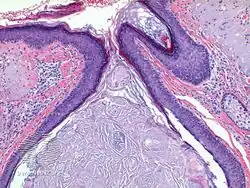

Chronic exposure to ultraviolet light can result in skin thickening as well as elastic destruction of the skin. At least in one instance, the occupational exposure to the UVA light of the sun (UVB is blocked by many car windows) resulted in skin destruction on one side of the face.[2] Microscopically, Favre–Racouchot displays multiple dilated follicular cysts/milia and open comedones with severe solar elastosis in the background dermis.

Favre–Racouchot syndrome-pathology -